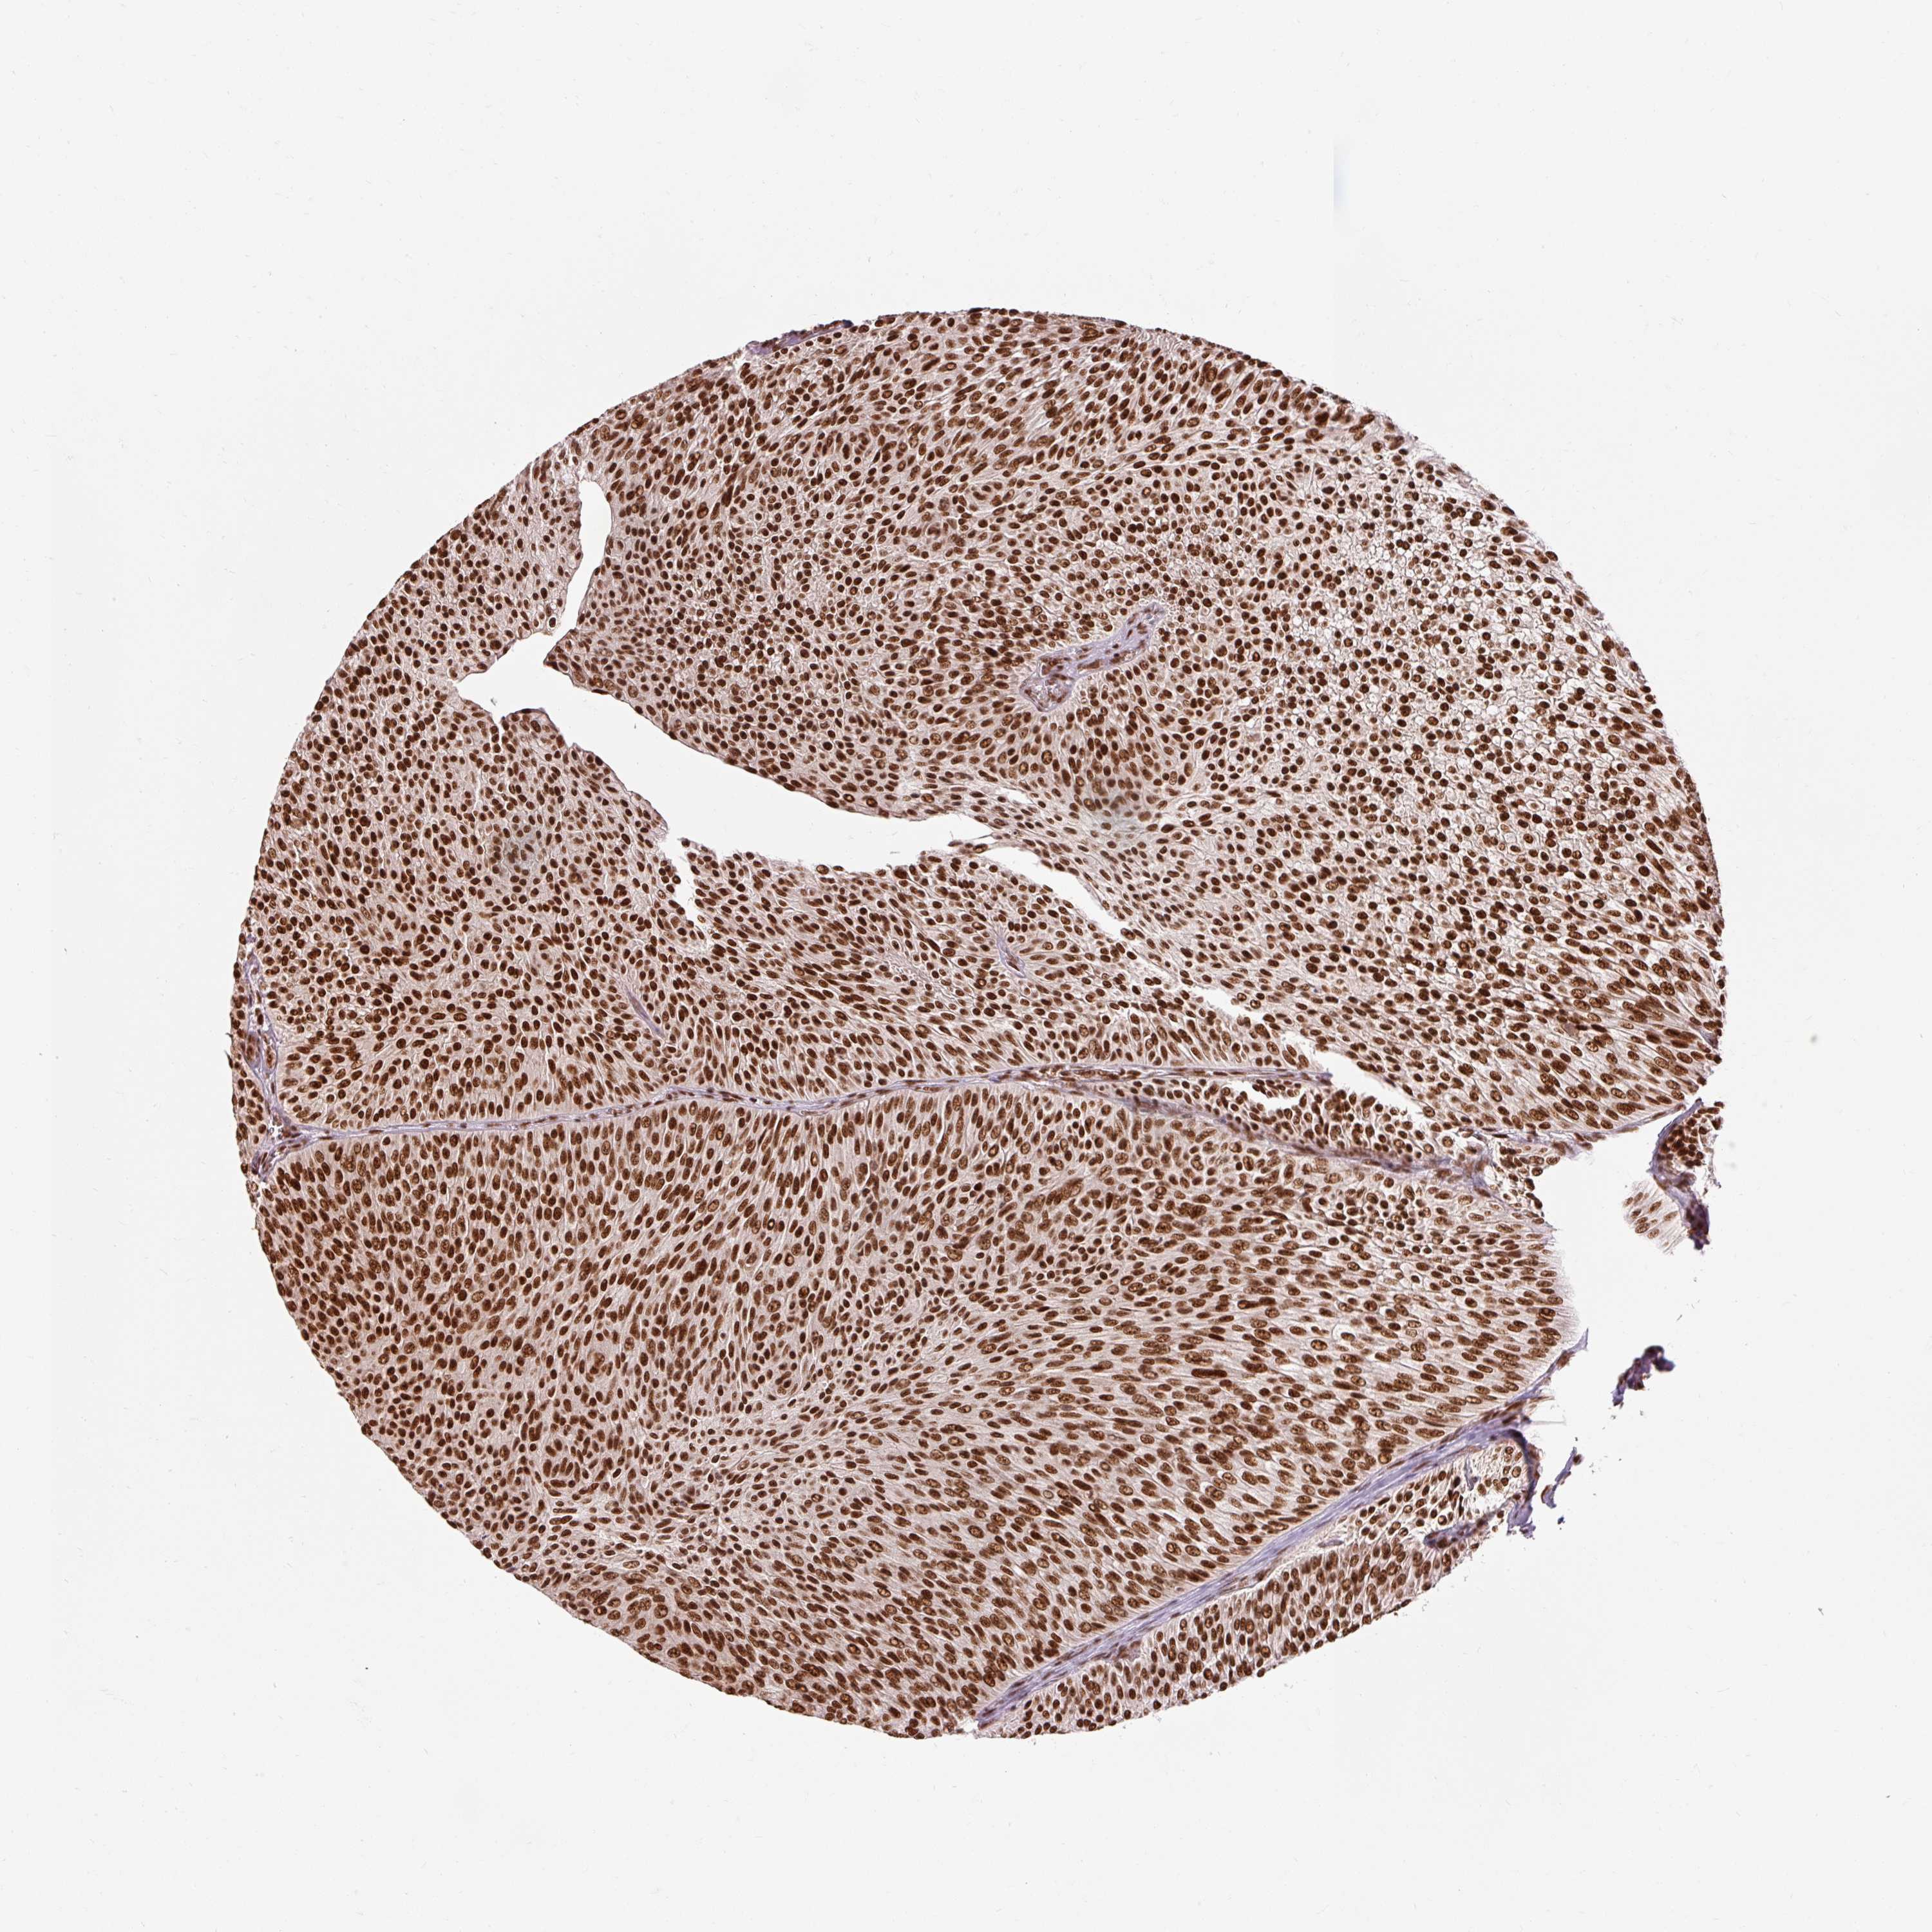

UROTHELIAL CANCER - Protein expressioni

A mouse-over function shows sample information and annotation data. Click on an image to view it in a full screen mode. Samples can be filtered based on level of antibody staining by selecting one or several of the following categories: high, medium, low and not detected. The assay and annotation is described here.

Note that samples used for immunohistochemistry by the Human Protein Atlas do not correspond to samples in the TCGA dataset.

Antibody stainingi

Antibody staining in the annotated cell types in the current human tissue is reported as not detected, low, medium, or high, based on conventional immunohistochemistry profiling in selected tissues. This score is based on the combination of the staining intensity and fraction of stained cells.

Each image is clickable and will lead to virtual microscopy that enables deeper exploration of all samples and also displays staining intensity scores, fraction scores and subcellular localization as well as patient and tissue information for each sample.

Antibody HPA052589

Staining

High

Medium

Low

Not detected

Intensity

Strong

Moderate

Weak

Negative

Quantity

>75%

75%-25%

<25%

None

Location

Nuclear

Cytoplasmic/membranous

Cytoplasmic/membranous,nuclear

Urothelial carcinoma, High grade

Urothelial carcinoma, NOS

Urothelial carcinoma, Low grade